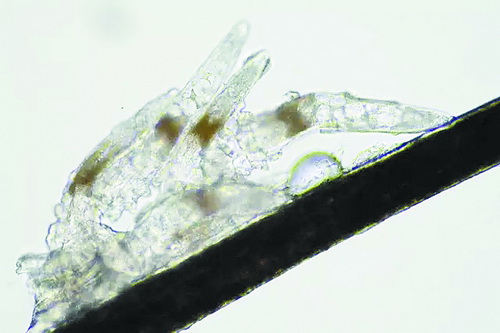

顯微鏡下長在睫毛中的螨蟲

冬天來了,氣溫降低,睫毛上的“隱形殺手”蠕形螨卻沒有要冬眠的意思。廈門大學附屬廈門眼科中心11月初開設蠕蟲性瞼緣炎門診以來,每天來查螨的市民都特別多,短短一個多月,已有近千人在顯微鏡下見到長期寄居在自己睫毛上,朝夕相處,卻素未謀面的蠕形螨。

蠕形螨怎么就跑進眼睛里了呢?原來,蠕形螨以吃角質(zhì)蛋白、油脂為生,而我們的睫毛和瞼板腺等地方油脂分泌旺盛,正是螨蟲寄居的理想場所。蠕形螨有兩種,一種是寄生在睫毛、眉毛毛囊里的毛囊蠕形螨,一種是寄生在皮脂腺和瞼板腺內(nèi)的皮脂蠕形螨,它們在眼睛里吸食油脂、吞噬上皮細胞、產(chǎn)卵、排泄,會引發(fā)一系列不良反應。